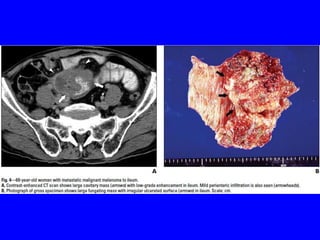

• The radiologic appearance mainly depends on the histologic

characteristics of the lesion, including the degree of vascularity

relative to the growth rate&the desmoplastic capability.

• Although most GIT metastases are encountered in patients with

widespread metastases & known primary lesions, they may

occasionally present as the initial manifestation of an occult

primary lesion, leading to diagnostic difficulty.

• Familiarity with CT findings of blood-borne metastases to GIT &

understanding disease spread pattern in common primary cancers

will help in detecting metastatic disease & minimizing misdiagnosis

for another metachronous malignancy.